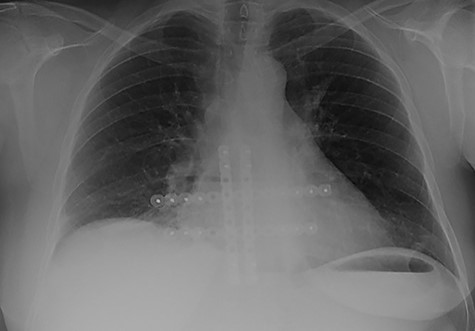

The second case at our institution was a 52-year-old woman with a history of left breast carcinoma treated for which she had undergone left wide local excision and sentinel node biopsy. Due to uncertainty regarding margins, she required a re-resection of her left breast tissue. She completed adjuvant radiotherapy and received maintenance hormonal therapy. She presented 8 months following her radiotherapy with sternal pain and positron emission tomography–computed tomography (PET–CT) imaging demonstrated localized uptake within the sternum (Fig. 3). Biopsy demonstrated proven recurrence of metastatic breast cancer. She was seen in clinic and counselled for partial sternectomy and reconstruction. She underwent partial sternectomy and underwent reconstruction with Synthes® plates. Her post-operative recovery was unremarkable. Post-operative histology was consistent with metastatic breast carcinoma, which was completely excised. The patient made an uncomplicated recovery and was seen in the outpatient clinic with a satisfactory post-operative chest radiograph (Fig. 4).

CT–PET demonstrating increased metabolic activity within the sternal lesion.